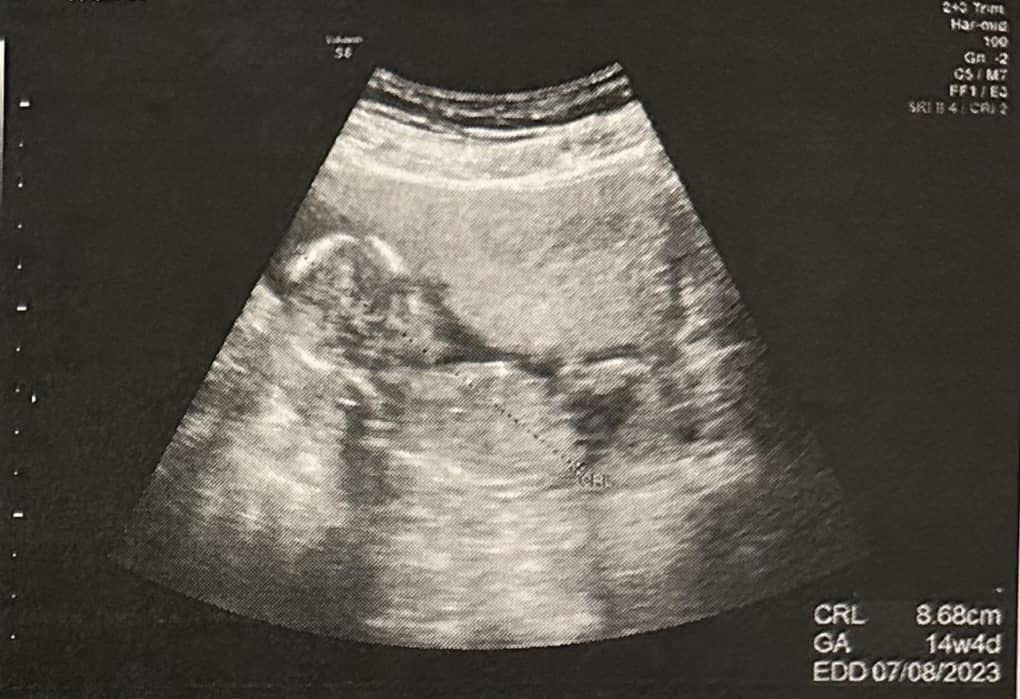

如今升格準人父的他,儘管工作再忙,都一定會陪老婆一起去產檢,記得當初看超音波的時候,當下曾有股想哭的衝動,並表示兒子照抄音波時看起來很調皮,「手一直遮住,後來瞬間照到小底迪,蠻感動的」,目前和老婆一起在物色新北2千萬左右的新房,希望到時孩子出生後,一家人能搬到更大的空間展開新生活,「我們預計懷孕時搬,但父母忌諱懷孕有胎神」。